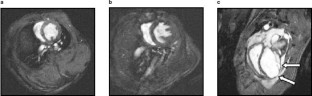

Fig. 2

Fig. 3

Fig. 4